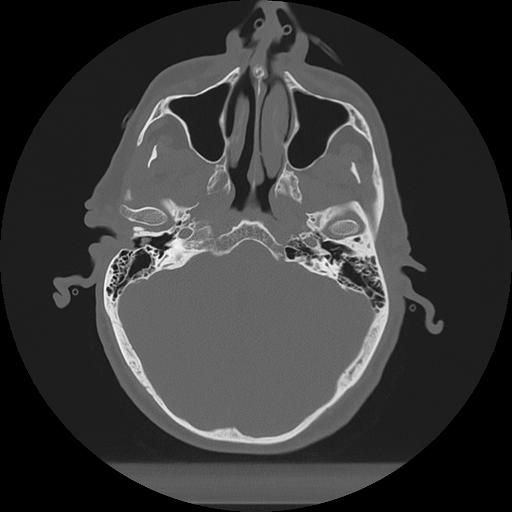

11 HUESO,,Axial,2.0,HUESO,,